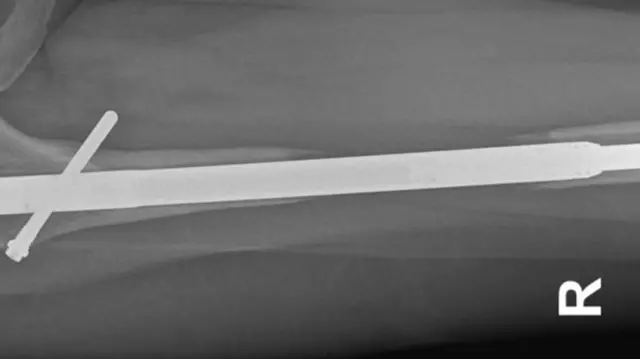

இது எலும்பியல் அறுவை சிகிச்சை நிபுணரான ஜீன்-மார்க் குய்செட் என்பவரால் நடத்தப்பட்டது. மூட்டு நீட்டிப்பு நிபுணரான அவர் ``Guichet Nail” என்ற நீளமான சாதனத்தை உருவாக்கினார். அவரே உருவாக்கிய இந்த உலோக கம்பியை கால் நீட்டிப்பு சிகிச்சைக்கு பயன்படுத்தினார்.

ஏனெனில், அறுவை சிகிச்சையின் போது, கால் எலும்புகள் இரண்டாக பிளக்கப்பட்டு, உள்ளே உலோக கம்பி பொருத்தப்பட்டுள்ளது.

உலோக கம்பிகள் அவற்றின் நீளத்தை அதிகரிக்கவும், எலும்பின் இரண்டு பகுதிகளை இழுக்கவும் படிப்படியாக நீட்டிக்கப்படுகிறது.

இந்த செயல்முறை மூலம் நோயாளியின் உயரம் அதிகரிக்கப்பட வேண்டும். சிகிச்சையின் போது உடைந்த எலும்புகள் படிப்படியாக மீண்டும் ஒன்றிணைந்து, இடையில் உள்ள இடைவெளியை நிரப்ப வேண்டும்.

அவரது இடது காலில் இருந்த கம்பி அவரது தொடை எலும்பு (மனித உடலின் வலிமையான எலும்பு) வழியாக உடைந்து வெளியே வந்துவிட்டது.

அவருடைய உலோகக் கம்பி ஊடுருவலால் அவரது தொடை எலும்பு இரண்டு எலும்புத் துண்டுகளாக மாறியிருந்தது.

"டாக்டர் குய்செட் அந்த கம்பியை வெளியே எடுக்கும்போது உடைந்து விட்டதாக என்னிடம் கூறினார்" என்று விவரித்தார்.